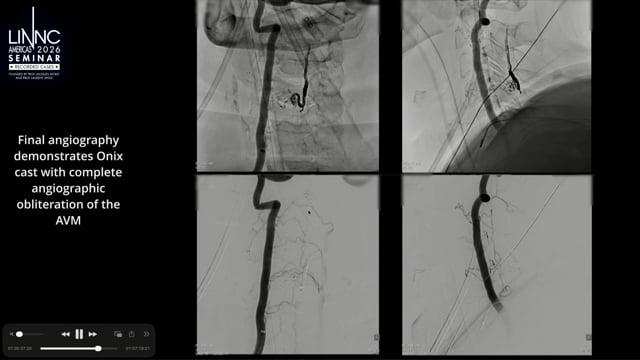

Dural AVF embolization - recanalising my way up the sequestrated sinus

Discover the case of a 35-year-old male presenting with left intracerebral hematoma. DSA showed dural arteriovenous fistula of the sequestrated sinus refluxing into the cortical vein. What was the chosen treatment? Watch now to find out!